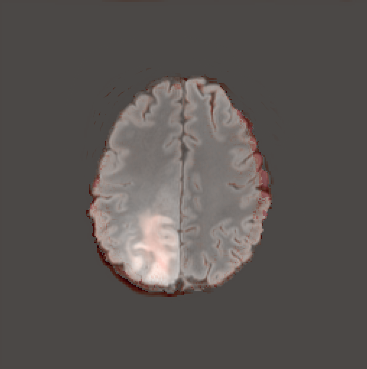

In this way, we are able to obtain a normal version of the given pathological image. In order to obtain an anomaly map, we first compute the difference between the original and the generated image and then apply erosion followed by dilation with a kernel to the resulting map, in order to remove noise, and finally dilation followed by erosion, with the same kernel, to close small holes in the map.

In Figures 2 and 4 we display examples of healthy images and anomaly maps obtained with the different approaches. We can observe that f-Ano GAN is not able to generate credible counterfactuals and generally produces images of poor quality and unrealistic appearance. On the other hand, the approaches based on diffusion models are able to create more high-quality results. However, the ones obtained with CG and CFG seem to present some artifacts, which may not only impact the realism of the counterfactual examples but also the precision of the anomaly maps obtained from them. In order to better quantify the capability of these methods to accurately segment pathological areas, we compute the Dice scores of the anomaly maps they generate.

We also test our approach on healthy samples. Ideally, we would like our generative process to act as the identity function when given a normal image as input. Some examples are shown in Figure 6, where we can observe that the changes introduced by our sampling technique are relatively minimal and Dif-fuse preserves the structure and general appearance of the images.